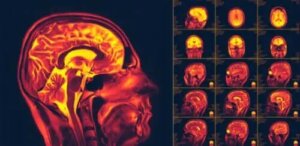

Neuroplastyczność mózgu, znana również jako plastyczność mózgu, jest jednym z najbardziej znaczących najnowszych odkryć na temat ludzkiego ciała. Jest to zdolność mózgu do zmian i dostosowania się do nowych zachowań lub doświadczeń.

Neuroplastyczność mózgu to zdolność neuronów do regeneracji. Dzieje się to pod względem zarówno anatomicznym, jak i funkcjonalnym. Tak naprawdę jest to proces obejmujący wiele reakcji biochemicznych i metabolicznych. Oznacza to również, że ma duży potencjał adaptacyjny.

Neuroplastyczność odnosi się do sposobu, w jaki nasz układ nerwowy musi tworzyć nowe połączenia. Ponadto, robi to w odpowiedzi na nowe bodźce, informacje, a nawet w celu leczenia uszkodzeń w starych połączeniach.